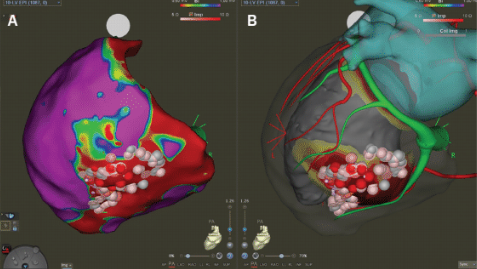

An example of a VT ablation performed using cardiac imaging is shown in Figure 1. A cardiac CT processed by inHEART is accompanied by an intracardiac ultrasound image. This patient had a large inferobasal left ventricular aneurysm with recurrent VT despite extensive endocardial ablation. She was brought back to the EP laboratory, and epicardial access was obtained using CO2 insufflation via intentional coronary vein exit (Figures 2A-C), as described by Silberbauer.20 The area of scar targeted for epicardial ablation is shown in Figure 3. The patient has been free of VT for over 12 months since her epicardial ablation and without any complications from the procedure.